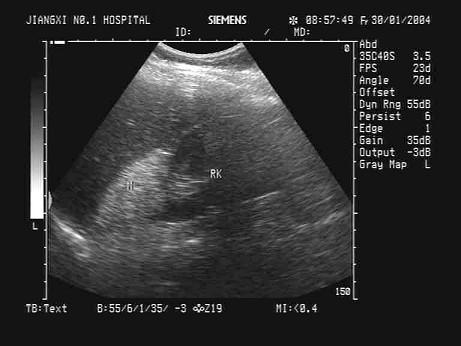

问题 某患者无明显不适,根据其肝右叶-右肾区超声声像图,最可能的诊断为?(?)

选项 A.正常图像 B.肾上腺髓样脂肪瘤 C.肾上腺嗜铬细胞瘤 D.肾脓肿 E.肾上腺腺瘤

答案 B